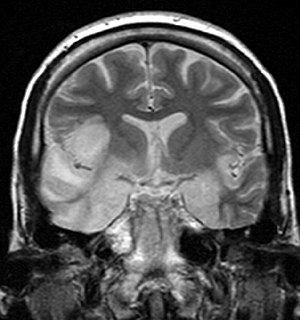

Coronal T2-weighted MR image shows high signal in the temporal lobes including hippocampal formations and parahippogampal gyrae, insulae, and right inferior frontal gyrus. A brain biopsy was performed and the histology was consistent with encephalitis. PCR was repeated on the biopsy specimen and was positive for HSV

Most individuals with HSE show a decrease in their level of consciousness and an altered mental state presenting as confusion, and changes in personality. Increased numbers of white blood cells can be found in patient's cerebrospinal fluid, without the presence of pathogenic bacteria and fungi. Patients typically have a fever[1] and may have seizures. The electrical activity of the brain changes as the disease progresses, first showing abnormalities in one temporal lobe of the brain, which spread to the other temporal lobe 7–10 days later.[1] Imaging by CT or MRI shows characteristic changes in the temporal lobes (see Figure). After the first symptoms appear, patients might lose their sense of smell. This can also be accompanied by the inability to read, write, or speak coherently, and understand verbal speech.[6]